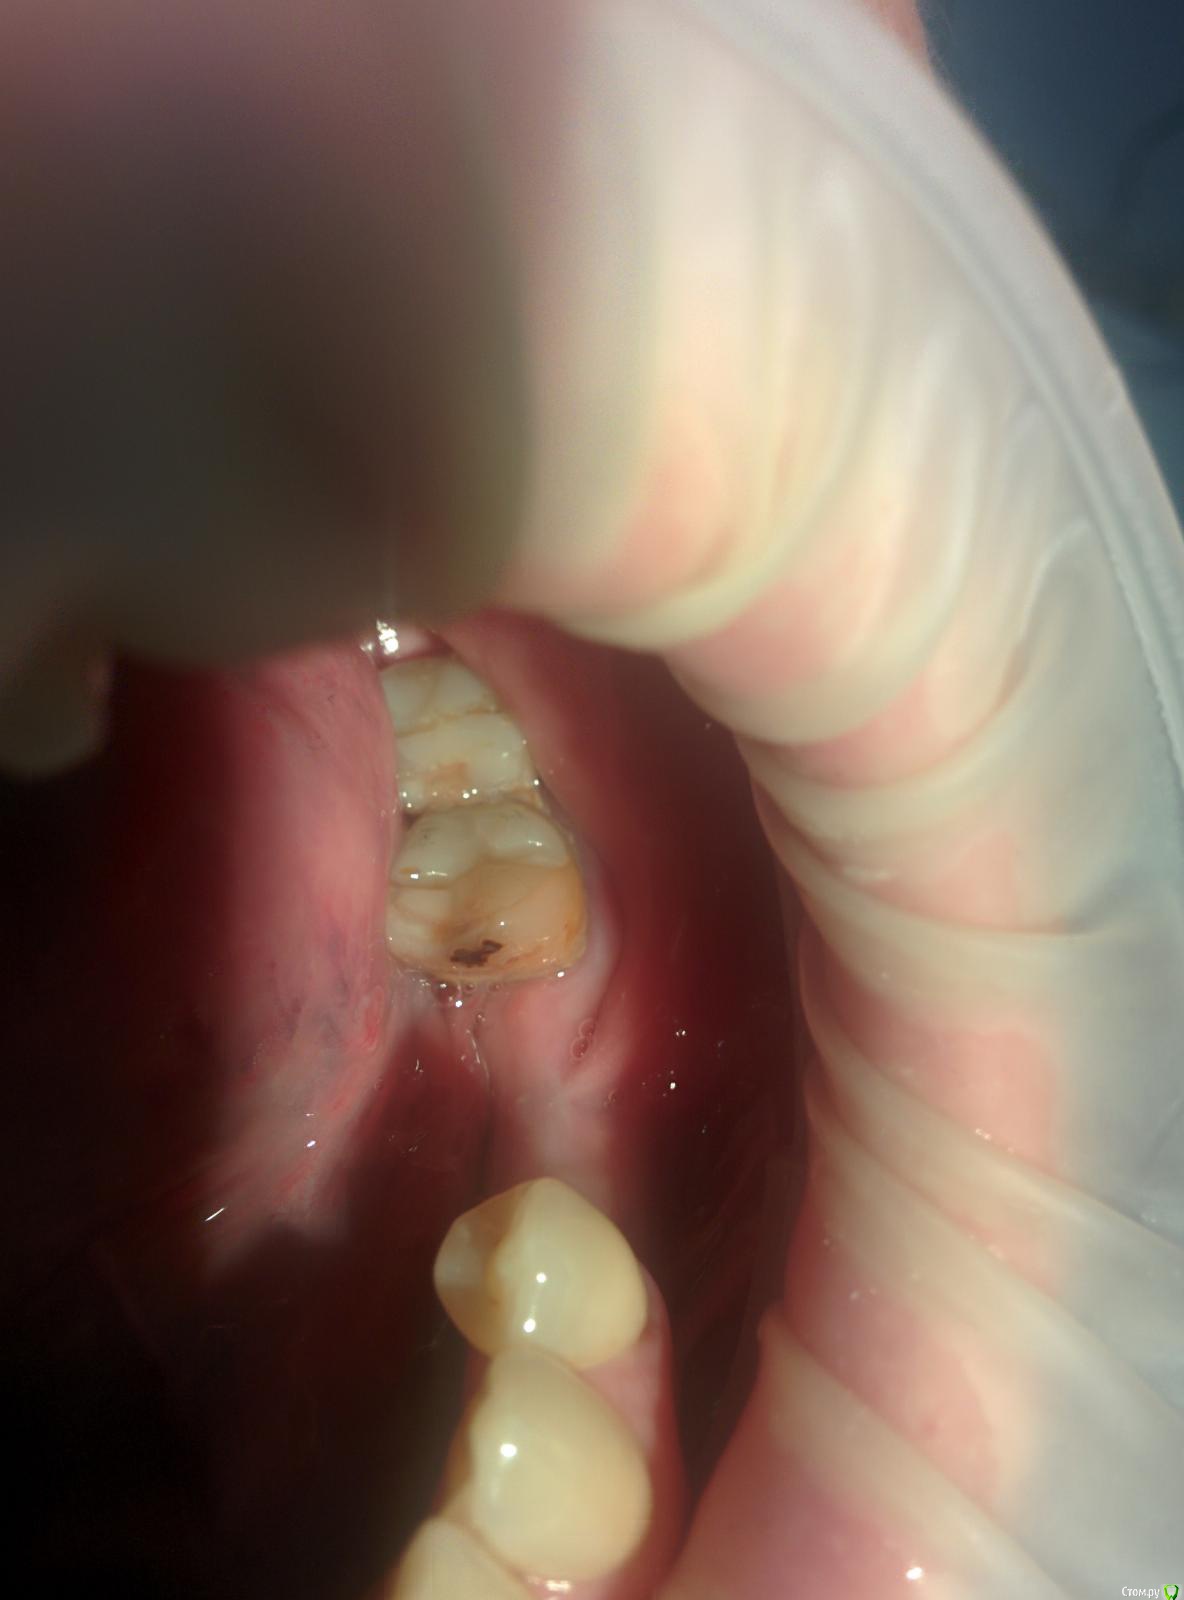

Марья Моревна Опубликовано 13 ноября, 2017 Поделиться Опубликовано 13 ноября, 2017 (изменено) Доброго начала недели,коллеги!Срочно нужен совет!Было поставлено : 35 - одномоментно без заполнения и 36.Через 4 мес.имеем:После.BMPТеперь планируется постановка мембраны остеопласт над 36 и коррекция мягких с вестибулярной стороны.А через 3 мес.- фдм.Правильный ли это план и у кого какие будут конструктивные(и критические) предложения?Спасибо. Изменено 13 ноября, 2017 пользователем Марья Моревна Ссылка на комментарий